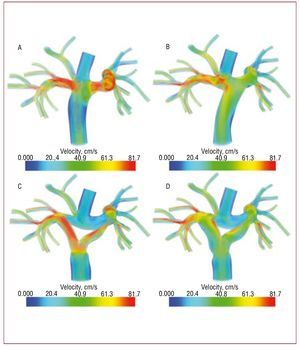

Current surgical practice for the Fontan procedure uses an extra-cardiac conduit to bypass the right side of the heart,39 with an offset of the IVC relative to the SVC (Figure 3B). Compared to the original "T-junction" design (Figure 3A), the offset design offers advantages of reduced energy losses and the ability to perform the surgery without cardiopulmonary bypass.52

Figure. 3. Modification of a patient-specific model to test competing surgical designs for the Fontan procedure: (A) original T-junction, (B) offset design, (C) Y-graft with smaller branches, and (D) Y-graft with larger branches. Colors show velocity magnitude from simulated hemodynamics at exercise. From Marsden et al.16

To improve on current Fontan designs, Marsden et al recently proposed a new Y-graft design for the extra-cardiac Fontan procedure.16 This new modification incorporates a Y-shaped graft to replace the cylindrical Gore-Tex tube grafts currently used to connect the IVC to the pulmonary arteries (Figures 3C and 3D). In this study, a patient-specific Fontan model was constructed from MR data. The inferior vena caval portion of the model was then replaced with 3 alternate designs: an offset between the superior and inferior vena cava, and 2 different sized Y-grafts. Several measures of performance were used to evaluate the proposed Y-graft design in simulations: energy efficiency, pressure levels, flow distribution to the lungs, and WSS. It was found that the Y-graft design demonstrated improvements in energy efficiency at rest and all levels of exercise, reduced SVC pressures and improved flow distribution.

Figure 4 shows a comparison of IVC flow distribution to the right and left pulmonary arteries with the offset design and the Y-graft design. Flow distribution was quantified using advanced particle tracking methods.36 Previous studies have shown that a yet undetermined hepatic factor is essential for normal lung development, and that the lack of this factor can lead to the development of arteriovenous malformations.53,54 The distribution of IVC flow will affect the concentration of hepatic factor present in the lungs. While it is not known what concentration is required for normal lung development, if all other factors are equal it is clearly desirable to distribute the flow (and, additionally, the relative "work" required by each lung) as evenly as possible. The proposed large Y-design was found to evenly distribute the IVC flow. In contrast, the offset design strongly skewed the flow towards one side.

Figure 4. Comparison of particle tracking for a traditional offset design and the proposed Y-graft design for the Fontan procedure. From Marsden et al.16